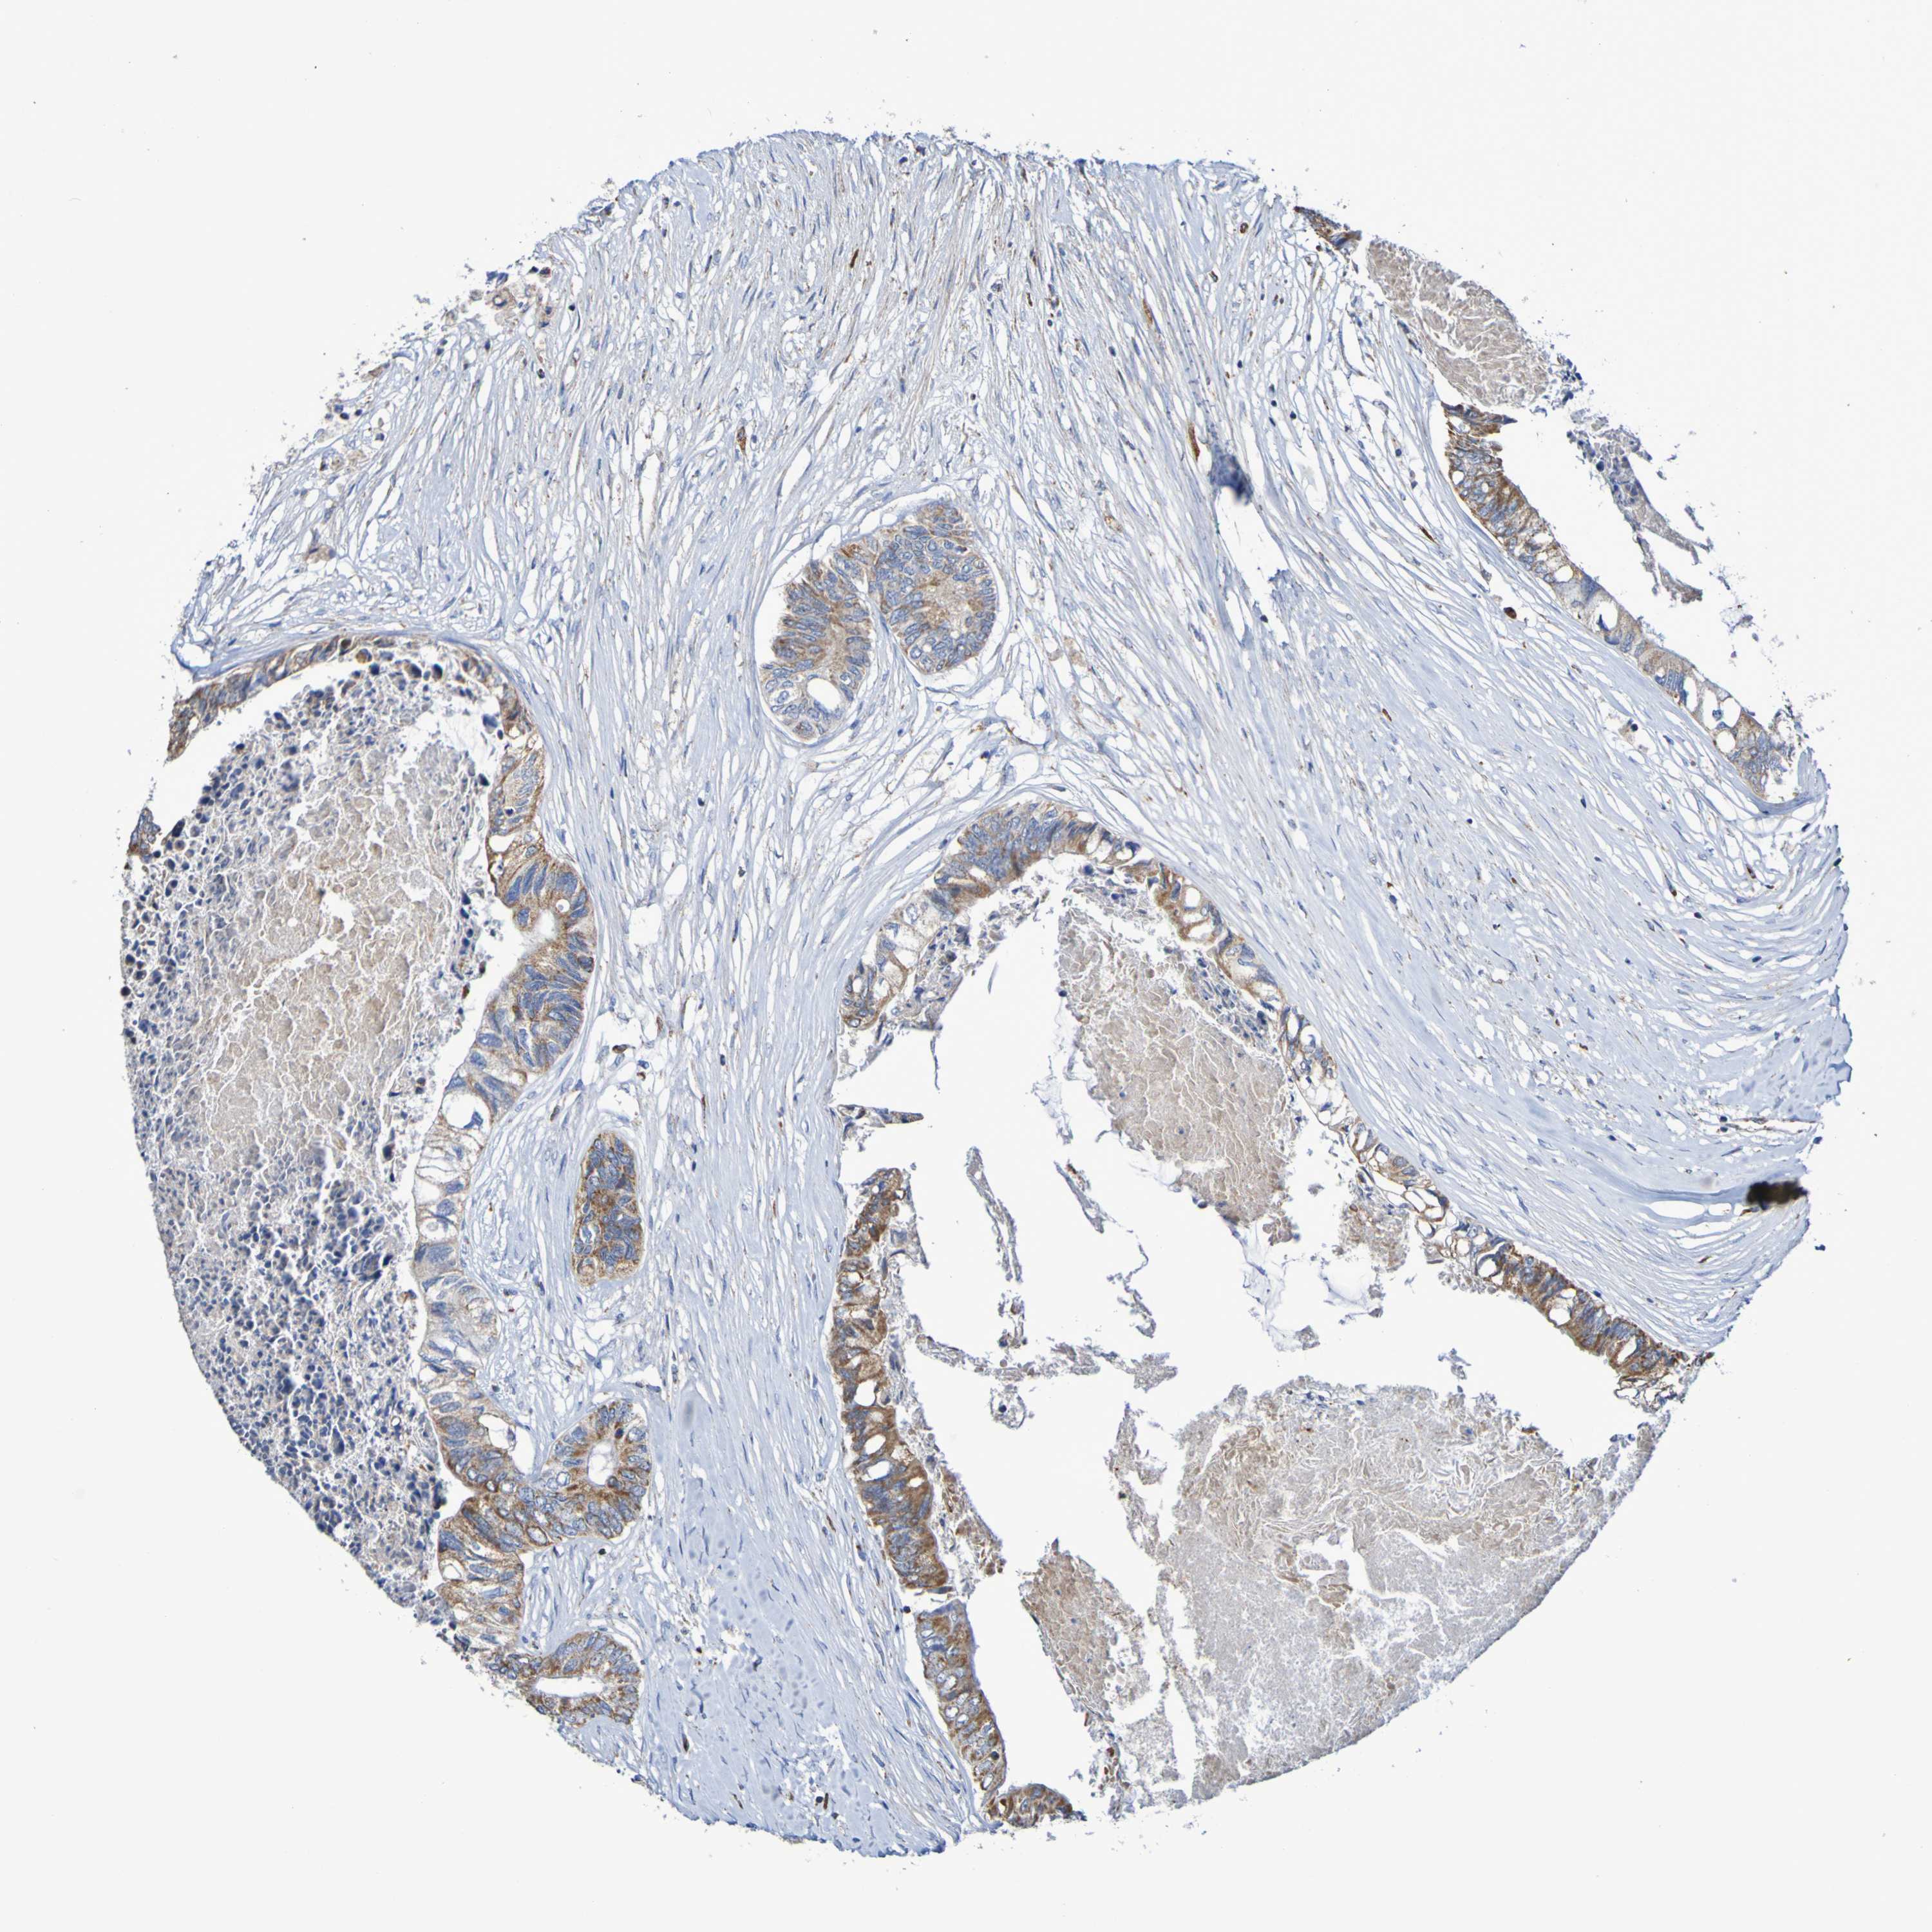

CANCER COLORECTAL CANCER Show tissue menu

Colorectal cancer

Human cancer

Colon adenocarcinoma